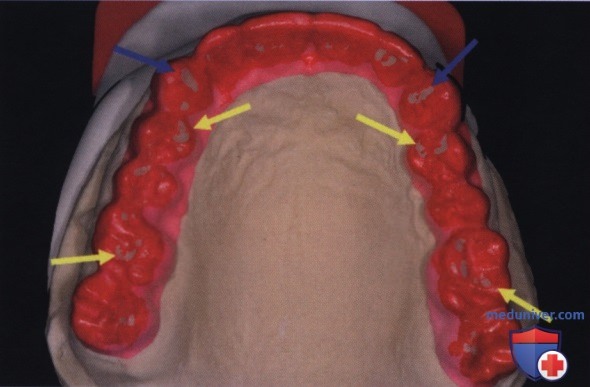

Рентгенография небного шва: Медицинские исследования и диагностика

Раздел: Фотопутеводитель